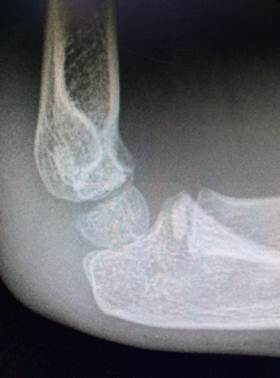

Область локтя в разном возрасте

Василий Оскарович Маркс говорил, что неподготовленный человек на

снимке локтевого сустава здорового ребенка найдёт восемь переломов. Очень даже

может быть – рентгенологическая картина локтя ребенка в возрасте от года до

четырнадцати лет насыщена ядрами окостенения и зонами роста, которые легко

принять за костный отломок или осколок, особенно если в анамнезе есть травма.

4 года – 6 лет

Завершение оссификации хряща метафизарной зоны плечевой кости и

контурирование зоны нахождения медиального надмыщелка. В 6 лет появляется ядро

окостенения медиального надмыщелка. Костная ткань начинает заполнять локтевой

отростк и его тень накладывается на тень метафиза плечевой кости на прямых

снимках. Головка лучевой кости имеет сформированную зону роста.

Возраст 6 лет. Появилось ядроокостенения медиального надмыщелка.

Хорошо прослеживаются основания венечного и локтевого отростков. На прямом

снимке тень локтевой кости находится

выше уровня суставной щели.